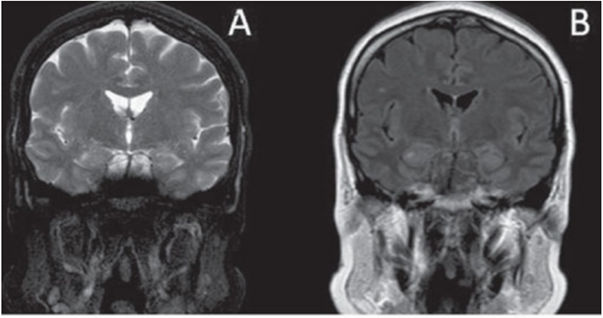

Paciente de 60 anos, sexo masculino, hipertenso, apresentou quadro de desorientação temporal e espacial de início súbito, acompanhado de cefaleia leve, sem perda de consciência, com duração de 12 horas. Foi submetido a exame de ressonância magnética do encéfalo dois dias após o início do quadro, estando disponíveis as seguintes imagens: A - T2; B - FLAIR; C - difusão; D - mapa de ADC.

Assinale a alternativa correta, que contém o diagnóstico para o quadro apresentado acima.